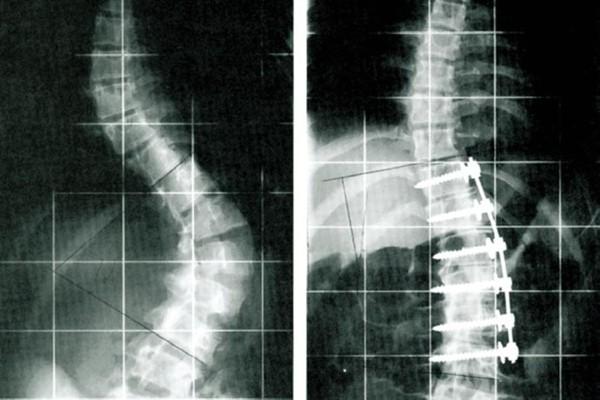

Zu einer operativen Versteifung der Wirbelsäule, auch Spondylodese genannt, raten Ärzte dann, wenn die Wirbelsäule eines Patienten derart instabil verändert ist, dass sich die damit verbundenen Beschwerden mit konservativen Maßnahmen wie beispielsweise der Physiotherapie nicht mehr mildern lassen. Der Eingriff verfolgt das Ziel, das erkrankte und operierte Wirbelsäulensegment absolut ruhig zu stellen. Hierzu werden mithilfe von Platten und Schrauben einzelne Wirbelkörper miteinander verbunden.

Ob eine anteilige oder komplette Spondylodese notwendig ist, hängt vom Umfang der Verletzung der Wirbelkörper und Wirbelsäule ab, über den eine Röntgenuntersuchung und eine Magnetresonanztomographie Auskunft geben. Während eine Teil-Spondylodese lediglich die Verbindung einzelner benachbarter Wirbel vorsieht, wird bei der vollständigen Wirbelsäulenversteifung ein längerer Abschnitt versteift.

Je nachdem, ob die etwa zweistündige Spondylodese aus Richtung Bauch oder von hinten über den Rücken vorgenommen wird, wird der Patient nach Erhalt der Vollnarkose auf dem OP-Tisch gelagert. Nachdem der Arzt den zu operierenden Bereich der Wirbelsäule freigelegt hat, ist oftmals die Entfernung einiger Teile des knöchernen Wirbelkörpers oder mitunter ganzer Wirbelkörper erforderlich, bevor der Chirurg spezielle Schrauben und Platten zur Stabilisierung implantieren kann.